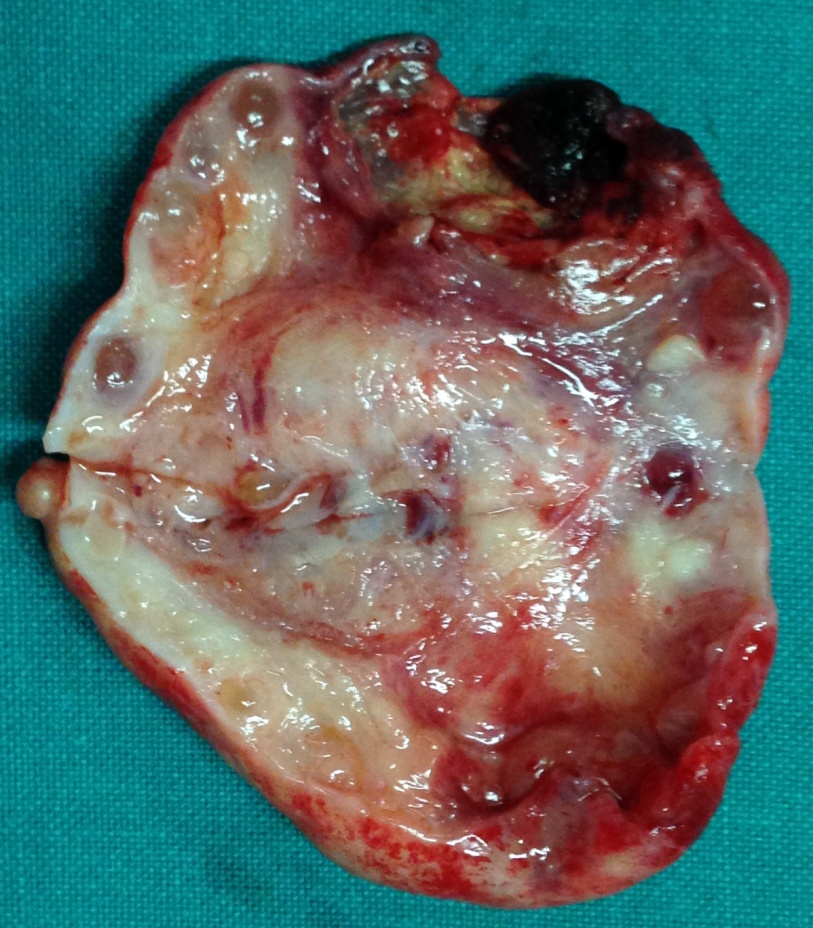

Χειρουργικά παρασκευάσματα εξαιρεθέντων ενδομητριωμάτων (Ευγενική παραχώρηση Dr. V. Penopoulos)